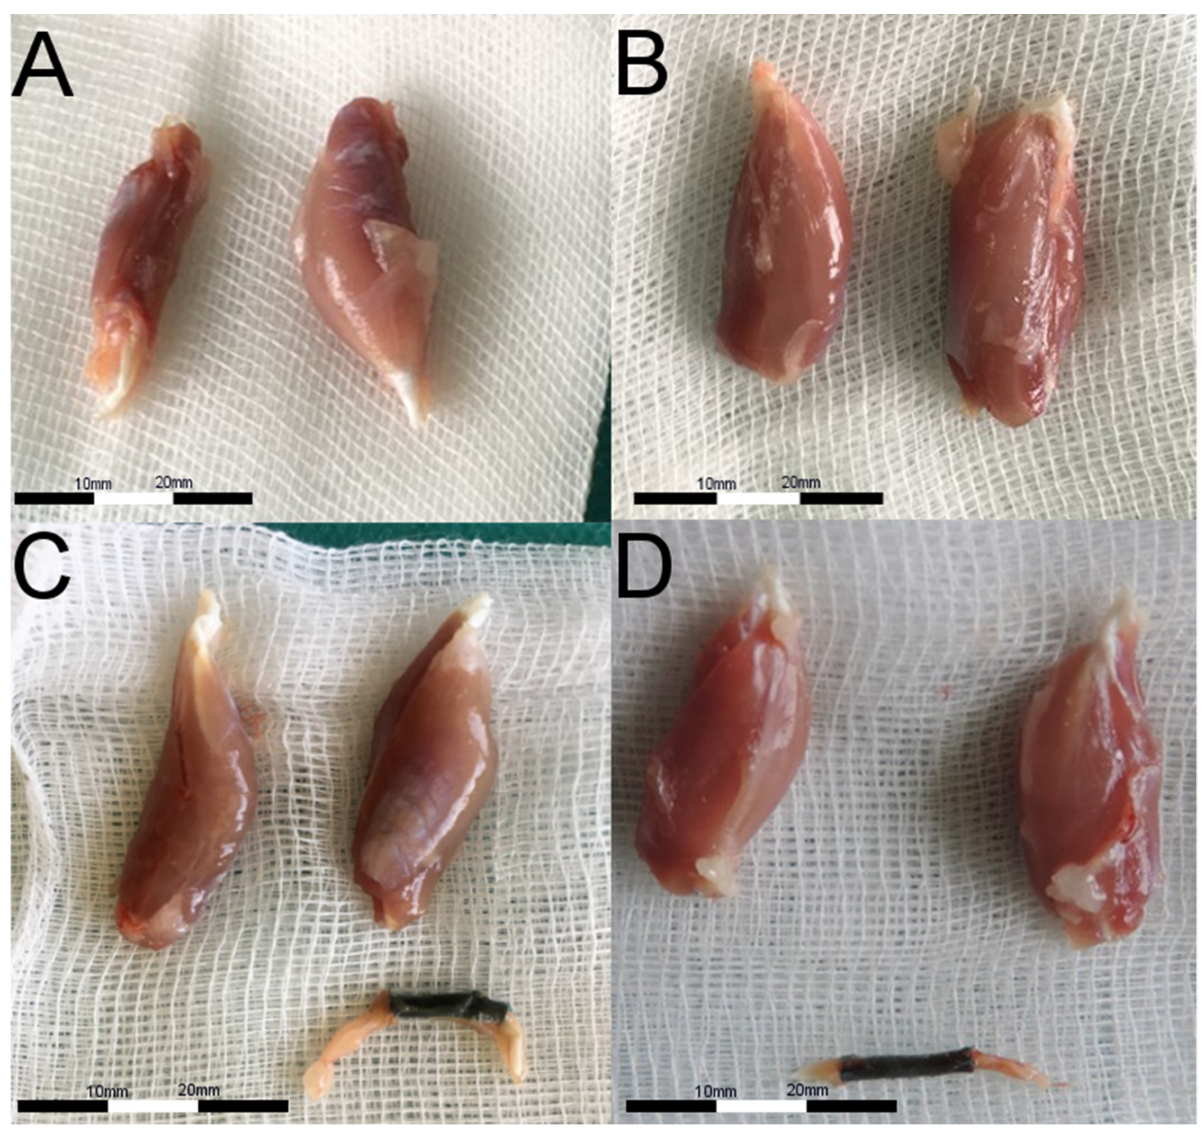

2.3. Animal Study and SFI

4.4.5. Animal Study Design